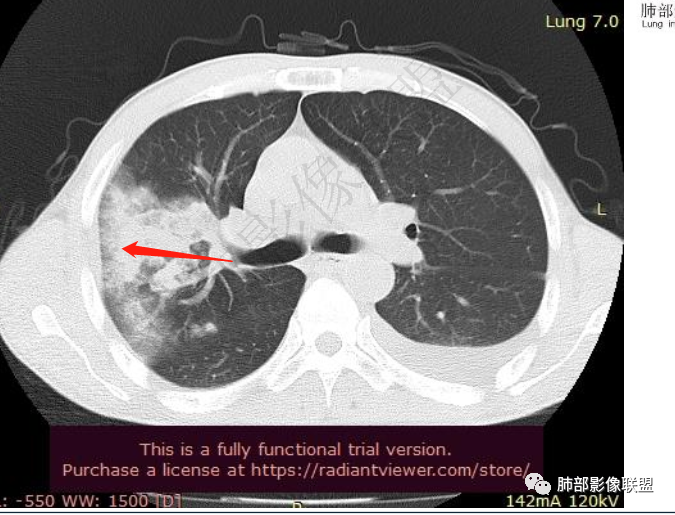

双肺多发大小不等结节影,边缘伴有磨玻璃影,边界欠清,部分与血管束相连,支气管似有穿行病灶内,结节有融合,左肺下叶厚壁空洞,伴有反晕征,左侧胸水,临床中年男性,发热40℃,CRP增高,感染性病变,1:类鼻疽伯克霍尔德菌(好发海南,影像表现也符合)

影像:双肺多发结节、实变影,大部分病灶边界不清,分布相对随机,左下肺坏死空洞形成,伴左侧胸水。

影像表现:双肺弥漫分布斑片影、实变影、磨玻璃影、结节影,晕征、反晕征,随机分布,部分病灶空洞形成前兆,左侧胸腔积液。

影像表现:双肺多发结节、实变影,大部分病灶边界不清,随机分布趋势,左下肺“反晕征”,似有形成空洞趋势。左侧胸腔积液。治疗后复查 ,大部分病灶吸收好转,呈较为典型血播分布,肝脏低密度块影,边界不清,符合肝脓肿。